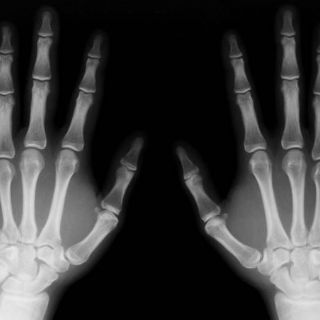

La cantidad de masa ósea está determinada por el equilibrio entre dos tipos de células: los osteoblastos, que intervienen en la creación del nuevo tejido óseo, y los osteoclastos, que lo degradan.

En la investigación japonesa, los ratones con dosis altas de vitamina E perdieron masa ósea, un dato que los científicos consideran que se debe a que este componente aumenta el número de osteoclastos, lo que a su vez se traduce en que se destruye más hueso del que se crea.